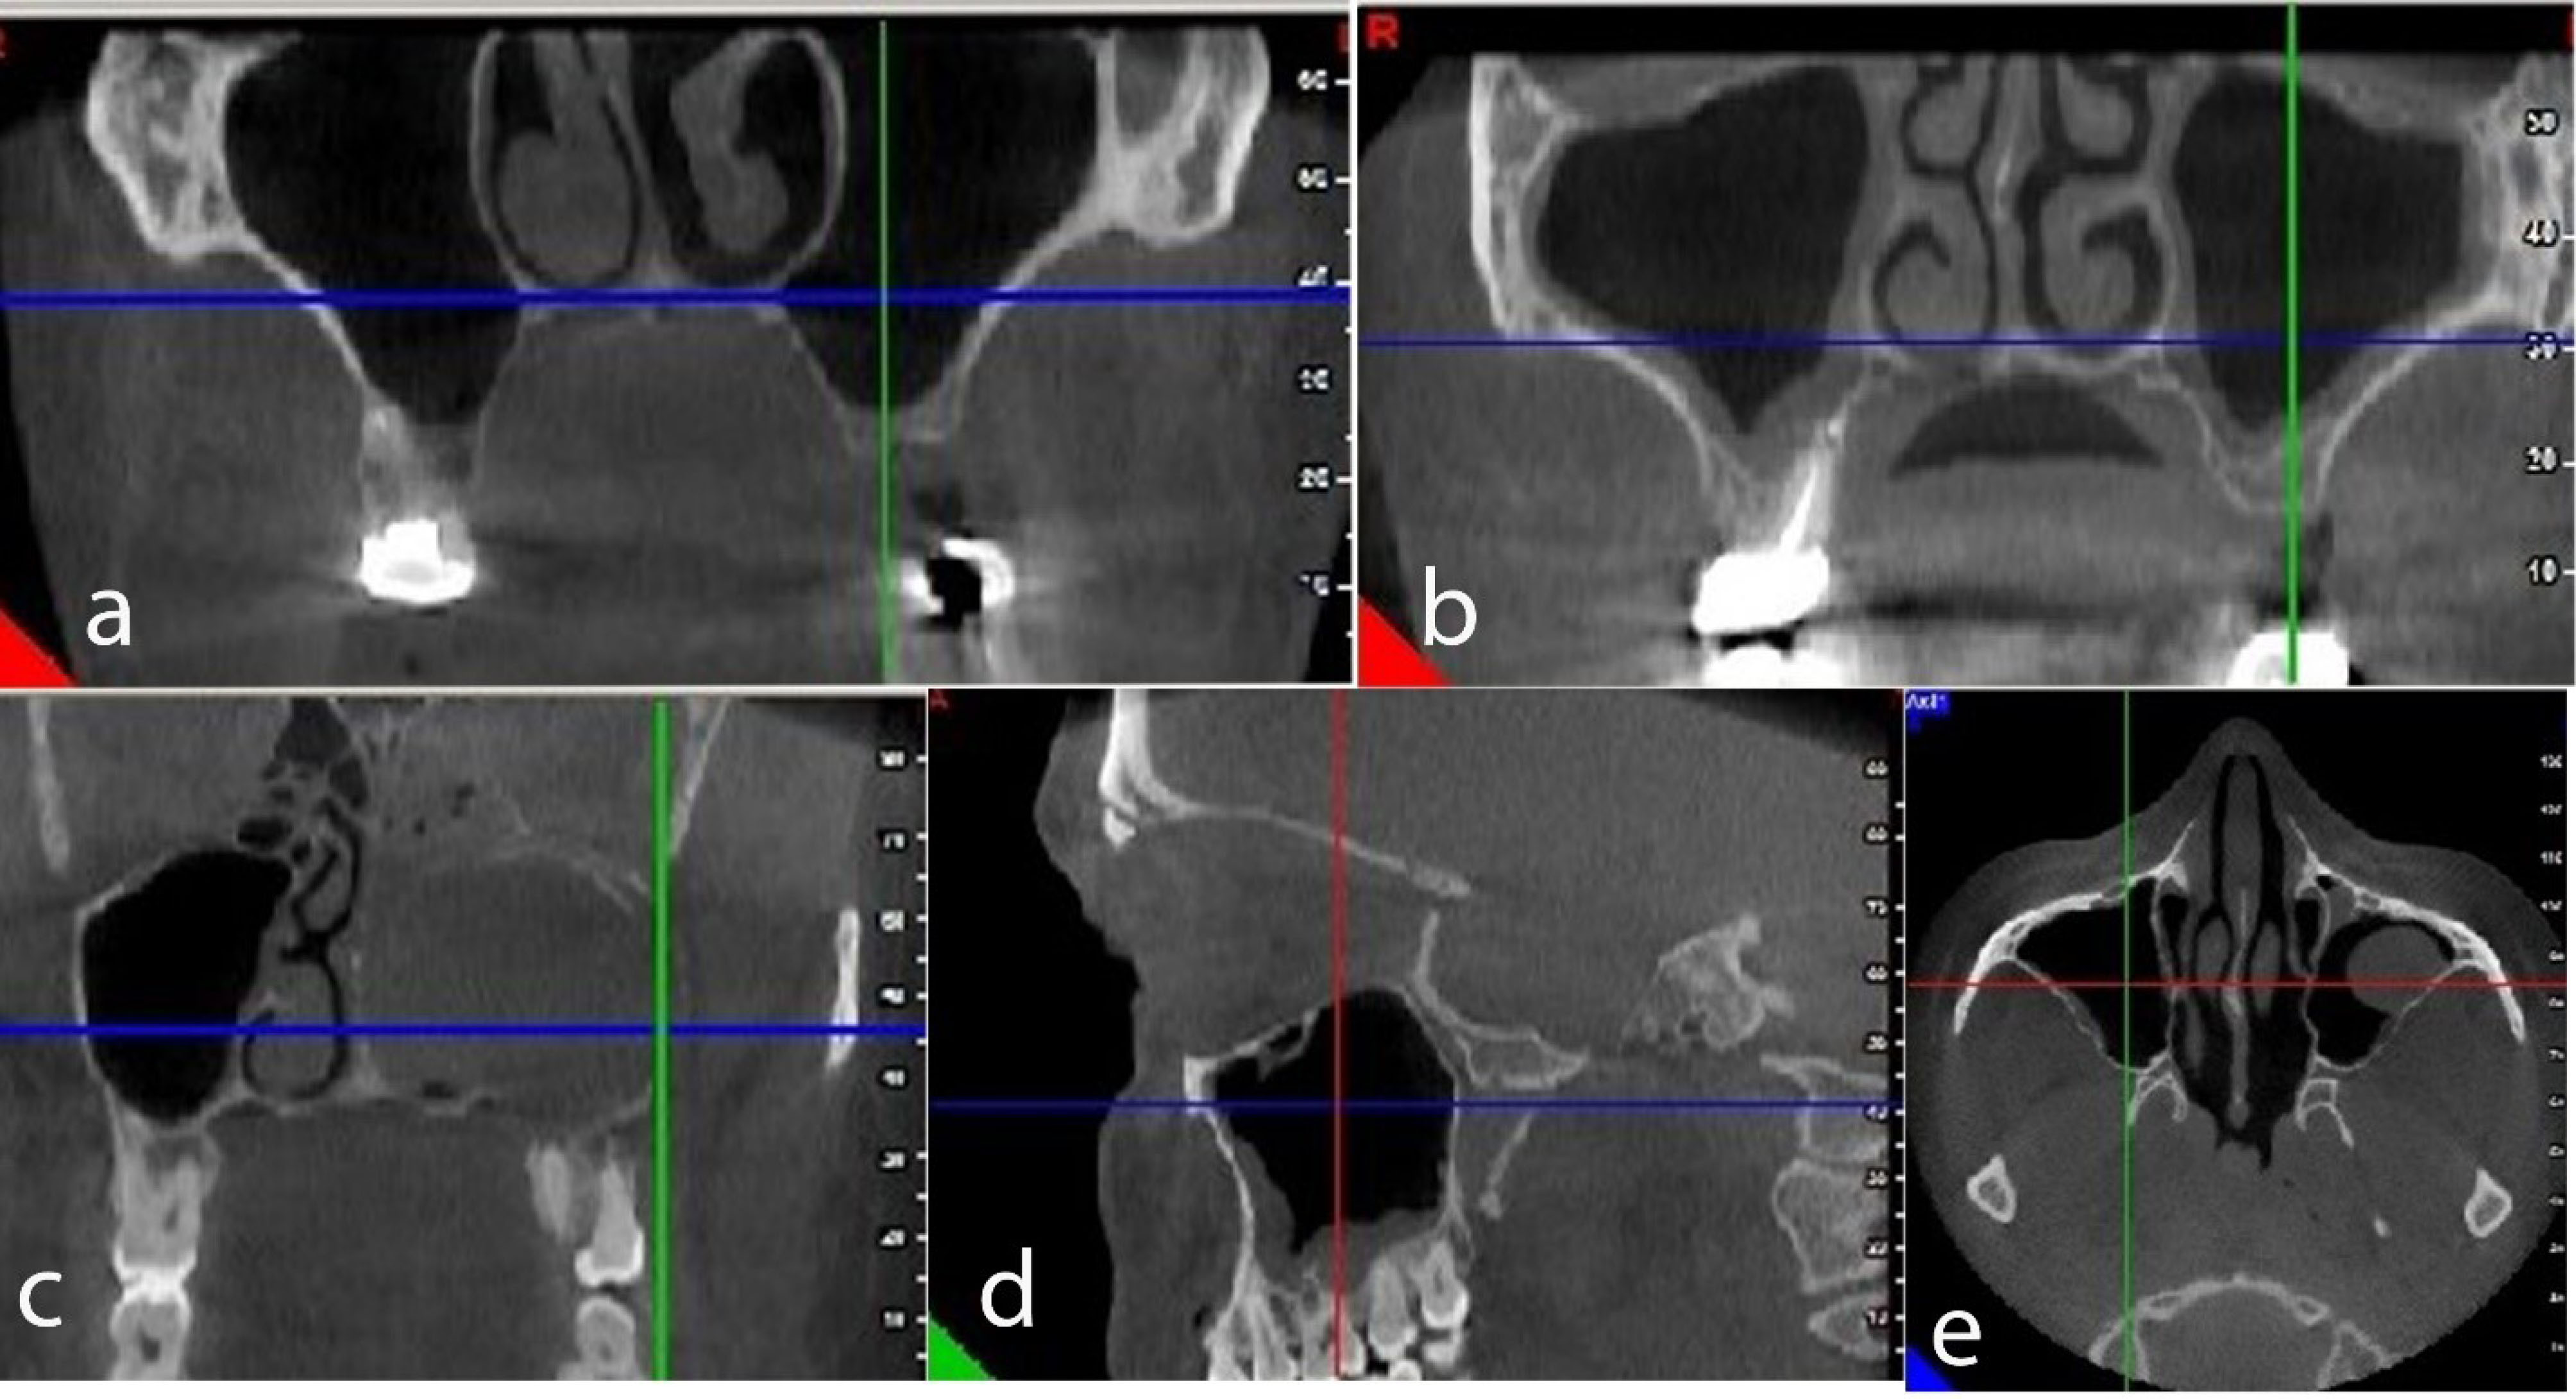

Of 140 subjects in the present study, 58 (41.8%) were male, and 82 (58.5%) were female, with a mean age of 46 years and an age range of 18–81 years. The patients’ maxillary dentition statuses were as follows: 44 (31.4%) had full dentition, 22 (15.7%) exhibited complete edentulism, and 74 (52.9%) had partial edentulism. No pathologic conditions were identified in 36.5% of CBCT images, while 63.5% showed pathologic findings. Table 1 presents the pathologic findings in maxillary sinuses on the CBCT images of patients. The most and the least frequent pathologic findings in maxillary sinuses were mucosal thickening (31.4%) and polypoidal mucosal thickening, respectively (Figure 1).

Figure 1.

(a) Bilaterally healthy maxillary sinus in axial view. (b) Bilateral mucosal thickening of the maxillary sinus in axial view. (c) Complete opacification of the left maxillary sinus in the axial view. (d) The polypoidal mucosal thickening of the right maxillary sinus in sagittal view. (e) The retention cyst of the left maxillary sinus in axial view.